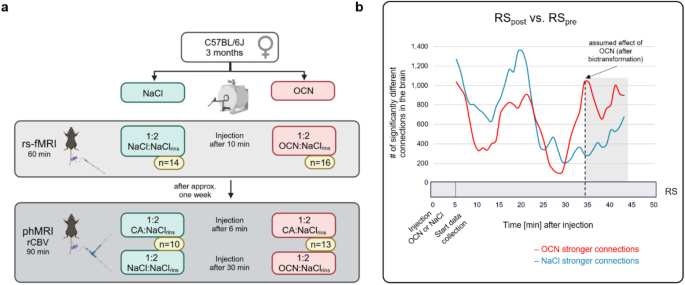

Fig. 6 shows FROC curves for each CT series in the internal validation dataset. The sensitivities for lesions ≥6 mm and lesions ≥10 mm were 0.815 and 0.883, respectively, when the allowed number of FP lesions per image was three. However, the sensitivities for lesions 6 to 10 mm when three or four FP lesions were allowed were low, with values of 0.738 and 0.785, respectively.

Sensitivities of the internal validation dataset based on CT series by FROC analysis. Sensitivity was evaluated in one position.

Fig. 7 shows FROC curves for the CT images of the Aizu and Kamigoto datasets. The sensitivities for lesions ≥6 mm and lesions ≥10 mm when four FP lesions were allowed were 0.755 and 0.810 with the Aizu dataset and 0.729 and 0.802 with the Kamigoto dataset, respectively. It was also confirmed that the sensitivity increased when the allowed number of FP lesions was increased. However, the sensitivities for lesions 6 to 10 mm were 0.625 and 0.593 when four FP lesions were allowed and 0.675 and 0.689 when eight FP lesions were allowed, respectively; these values were considered low.

Sensitivities of the external validation dataset per CT series by FROC analysis. Sensitivity was evaluated in each supine or prone position.

Fig. 8 also shows FROC curves per patient in the external validation dataset. Regarding the detection performance for each patient, if a correct lesion could be detected in either the supine or the prone position, then this was considered detection success, and the sensitivity was calculated. The number of FP lesions was the average value of the lesions detected in the supine and prone positions. The sensitivities for lesions ≥6 mm and lesions ≥10 mm when four FP lesions were allowed were 0.835 and 0.894 with the Aizu dataset and 0.848 and 0.866 with the Kamigoto dataset, respectively. Using this method, the sensitivity improved compared to that observed when evaluating each CT series in one position. Additionally, even for 6 to 10 mm lesions, the sensitivities when four FP lesions were allowed were improved, with values of 0.684 and 0.816, respectively. During the evaluation per patient, a plateau of the sensitivity was confirmed even after increasing the allowed number of FP lesions.

Sensitivities of the external validation dataset per patient by FROC analysis. Regarding the sensitivities for each patient, if a correct lesion could be detected in either the supine or the prone position, then this was considered detection success, and the sensitivities was calculated.

A comparison of the sensitivity using the CT series with one position and the sensitivity for each patient in two positions is shown in Table 3. There was no difference in the sensitivities obtained in the supine and prone positions using both the Aizu and Kamigoto datasets when the number of FP lesions was allowed to be as high as 4 or 8. When comparing the sensitivity of the two position combinations with single position (supine or prone), we found that there was an improvement of 16.0 - 32.1% for FP=4 and 14.4 - 38.0% for FP=8, which were statistically significant at p < 0.05 in McNemar statistical test.